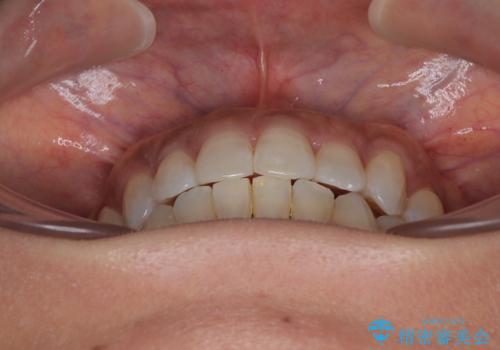

クロスバイトを治したい インビザラインによる矯正治療

咬合力による臼歯離開は顎間ゴムで改善されましたが、それとは別に下顎小臼歯がマウスピースに追従せず、補正のためのゴムかけが必要となりました。

大変なゴムかけ作業を頑張っていただき、無事に治療を終えることができました。